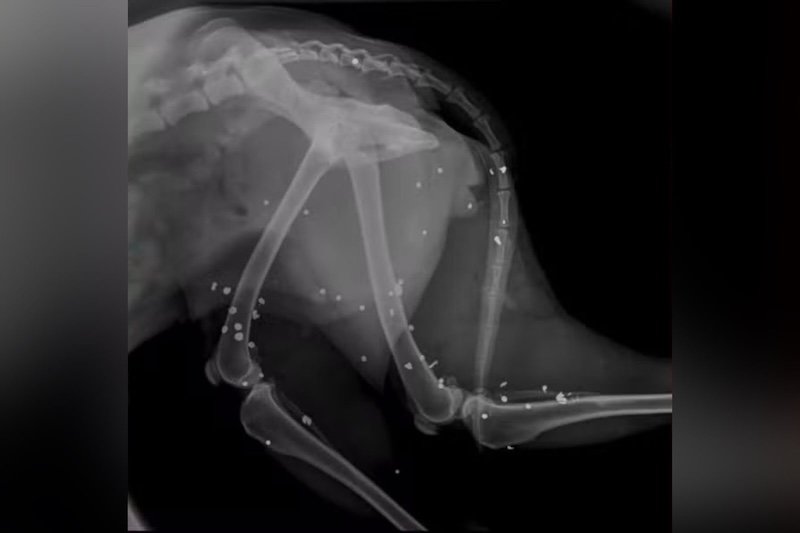

Cachorro morre e outro fica ferido após serem alvos de tiros de espingarda na Bahia (Foto: Reprodução)

O animal que sobreviveu foi resgatado e encaminhado com urgência para atendimento na clínica veterinária particular. Exames de raio-x apontaram que a cadela foi atingida por 43 chumbinhos — tipo de munição —, espalhados pelo corpo e próximos a órgãos vitais.